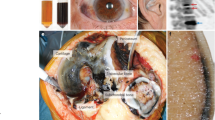

The accumulation of HGA in blood is central to the pathophysiology of the disease. It is proposed that HGA is oxidised to 1,4-benzoquinone-2-acetic acid (BQA) (Zannoni et al 1969). It is thought that BQA polymerises to form a melanin like pigment, which deposits in connective tissues in a process called ochronosis. The consequences of this chronic process are typically observed from the third to fourth decade of life and include spondyloarthropathy, rupture of ligaments/muscle/tendons, valvular heart disease including aortic stenosis and renal and prostate stones (Ranganath et al 2013). Acute metabolic decompensation can occur in AKU presenting with fatal complications, including oxidative haemolysis and or methaemoglobinaemia. It is the latter that will form the basis of this article. Herein the pathophysiology of why these acute complications may occur and the current literature will be reviewed.

There are eight cases in the literature reporting the acute fatal metabolic complications that can occur in AKU (Table 1). These include three patients that had oxidative haemolysis and methaemoglobinaemia (Abreo et al 1983; Suehiro et al 2007; Mullan et al 2015); three patients with methaemoglobinaemia (Liu and Prayson 2001; Uchiyama et al 2010; Miyasaka et al 2013) and two patients with oxidative haemolysis (Heng et al 2010; Bataille et al 2014). In all cases the outcome was death.

Common to all of these cases is that all patients had acute kidney injury (AKI), in some cases this was a new presentation and in others it occurred on a background of chronic kidney disease (CKD). Five of eight patients also presented with sepsis (Liu and Prayson 2001; Suehiro et al 2007; Uchiyama et al 2010; Miyasaka et al 2013; Mullan et al 2015). As previously mentioned the kidney plays a critical role in the elimination of HGA from the body, and thus it is reasonable to expect significant increases in the circulating concentration of HGA when kidney function is impaired. In all eight cases reported HGA was not measured, but is presumed to have been increased as kidney function was impaired.

Introne et al (2002) reported on a patient with AKU and CKD, where an increased plasma concentration of HGA was observed along with worsening clinically apparent ochronosis. Three months post renal transplantation the concentration of HGA was decreased from 126.3 to 43.7 μmol/L demonstrating the importance of kidney function in the elimination of HGA.

Interestingly, no acute oxidative haemolysis or methaemoglobinaemia was reported despite the very high concentrations of plasma HGA. This is in keeping with others (Venkataseshan et al 1992; Kazancioglu et al 2004; Faria et al 2012) where CKD has been reported in AKU and no fatal metabolic complications have been observed. This highlights that an elevated concentration of HGA alone is not responsible for the fatal metabolic complications that have been observed in other reported cases (Abreo et al 1983; Suehiro et al 2007; Mullan et al 2015; Liu et al 2001; Uchiyama et al 2010; Miyasaka et al 2013; Heng et al 2010; Bataille et al 2014). The authors’ hypothesise that multiple ‘insults’ to anti-oxidant defence mechanisms have a cumulative effect and are responsible for the reported haematological complications.

In all published cases where fatal metabolic complications were observed treatments utilised were unsuccessful. The reasons for this are not entirely clear. Treatments were based around renal replacement therapy (haemodialysis and haemofiltration), blood transfusion and anti-oxidant therapies including; vitamin C, N-acetyl cysteine (NAC) and methylene blue. Some of these therapies can act as pro-oxidant molecules, thus worsening the metabolic complications.